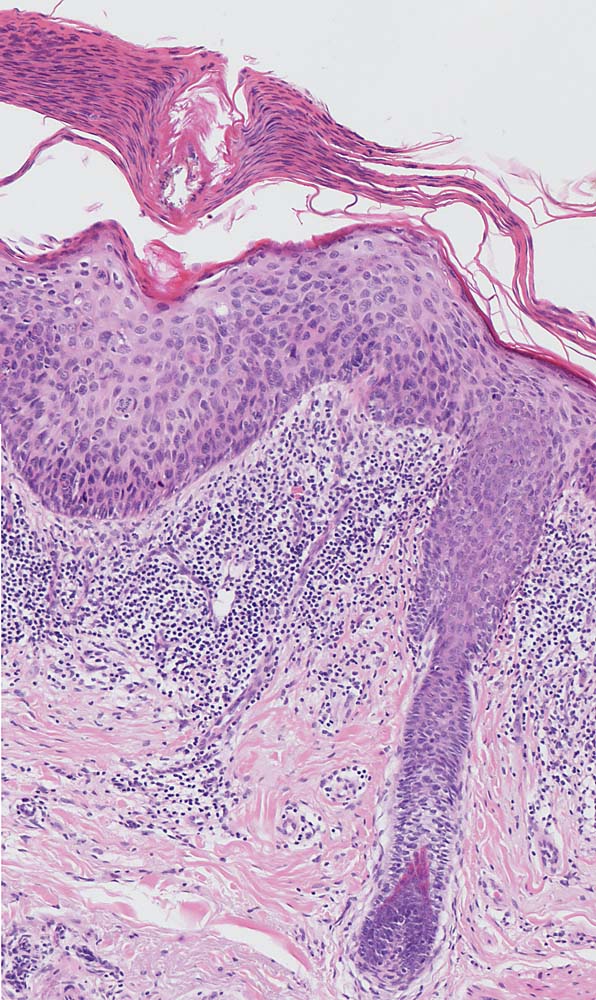

Die Epidermis zeigt obligat dysplastische Veränderungen. Die Dysplasie kann sich auf das untereste Epitheldrittel beschränken (leichte Dysplasie) oder die gesamte Epithelbreite betreffen (=bowenoide aktinische Keratose bzw. Carcinoma in situ). In der Dermis findet sich als Zeichen der chronischen UV Schädigung der Haut immer eine ausgeprägte solare Elastose. Das histologische Bild ist abgesehen von diesen zwei obligaten Befunden sehr variabel. Dyskeratotische Zellen und Mitosen finden sich häufig. Charakteristisch ist auch das Vorliegen einer alternierenden Para- und Orthokeratose, die unterschiedlich stark ausgeprägt ist. Manchmal findet man eine Atrophie der Epidermis mit schmalem Stratum corneum oder umgekehrt eine massive Hyperkeratose wie beim Cornu cutaneum. Akrosyringium und innere Abschnitte der Haarfollikel sind von den dysplastischen Veränderungen ausgespart. Die Epidermis zeigt häufig eine unregelmäßige Hyperplasie mit in das Stratum papillare reichenden Knospen. Bei Ausdehnung der Dysplasie entlang von Haarfollikeln in die Tiefe, können sich bei zu oberflächlicher Abtragung der Läsion Lokalredzidive ausbilden.

• Ausgeprägte solare Elastose (Zeichen der chronischen UV Schädigung).

• Epitheldysplasie: Reifungs- und Schichtungsstörung der Epidermis mit fokalem Polaritätsverlust der Keratinozyten, Atypien der Keratinozyten (hyperchromatische, pleomorphe und entrundete Zellkerne mit irregulärer Kernmembran und prominenten Nukleolen, vergrösserte Zellkerne mit hoher Kern-Plasmarelation) bis in obere Schichten der Epidermis. Dyskeratosen (hypereosinophile abgerundete Keratinozyten mit pyknotischem Zellkern als Zeichen der Verhornungsstörung). Crowding (überlappende Zellkerne).

• Zahlreiche, teils atypische (=multipolare) Mitosefiguren in allen Epidermislagen.

• Adnexstrukturen (Infundibulum und Akrosyringium) sind nur oberflächlich betroffen von den dysplastischen Veränderungen.

• Dermales chronisches lymphoplasmazelluläres Entzündungsinfiltrat